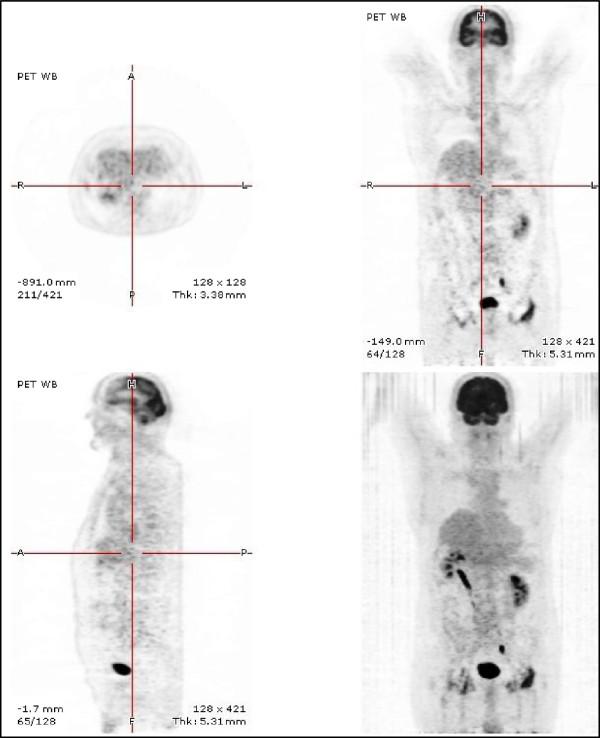

We report the 30-yr history of a well-documented human case of alveolar echinococcosis, with a lung lesion at presentation followed by the discovery of a liver lesion, both removed by surgery. Subsequently, within the 13 years following diagnosis, metastases were disclosed in eye, brain and skull, as well as additional lung lesions. This patient had no immune suppression, and did not have the genetic background known to predispose to severe alveolar echinococcosis; it may thus be hypothesized that iterative multi-organ involvement was mostly due to the poor adherence to benzimidazole treatment for the first decade after diagnosis. Conversely, after a new alveolar echinococcosis recurrence was found in the right lung in 1994, the patient accepted to take albendazole continuously at the right dosage. After serology became negative and a fluoro-deoxy-glucose-Positron Emission Tomography performed in 2005 showed a total regression of the lesions in all organs, albendazole treatment could be definitively withdrawn. In 2011, the fluoro-deoxy-glucose-Positron Emission Tomography showed a total absence of parasitic metabolic activity and the patient had no clinical symptoms related to alveolar echinococcosis.The history of this patient suggests that multi-organ involvement and alveolar echinococcosis recurrence over time may occur in non-immune suppressed patients despite an apparently "radical" surgery. Metastatic dissemination might be favored by a poor adherence to chemotherapy. Combined surgery and continuous administration of albendazole at high dosage may allow alveolar echinococcosis patients to survive more than 30 years after diagnosis despite multi-organ involvement.